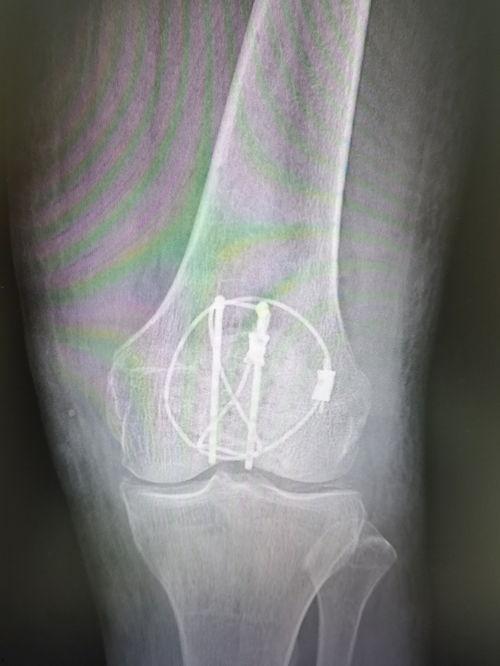

首先,让我们来了解一下这个让人头疼的髌骨骨折。髌骨,也就是我们常说的膝盖骨,位于膝盖前方,是人体最大的籽骨。它不仅起到保护膝关节的作用,还能帮助我们在运动时更好地发力。由于各种原因,髌骨骨折却成了不少运动爱好者的噩梦。